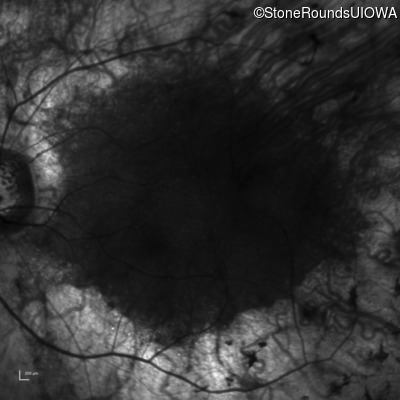

Infrared Fundus Photograph - Left - 20/40 +1

Exemplar